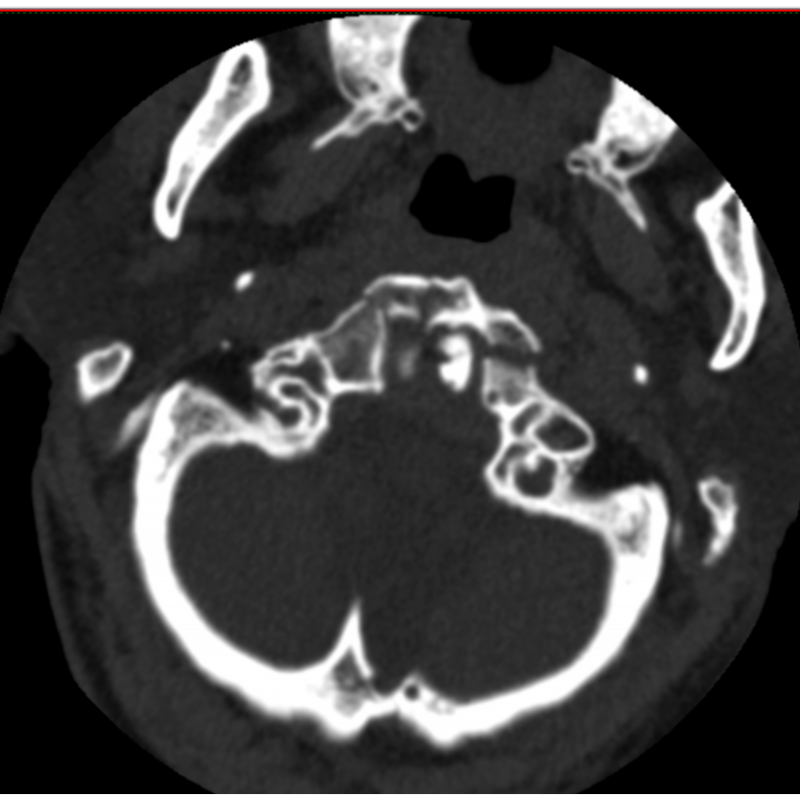

73岁的黄先生因不慎摔倒从山坡上滚下头面部先着地致“寰椎骨折”入住惠州市中心人民医院中文博彩平台分院(中文博彩平台人民医院)脊柱外科。入院时患者颈肩部、双上臂疼痛剧烈,伴有双上肢麻木感,活动受限。

术前检查

初期给予黄先生颈托外固定保守治疗,但考虑颈托限制活动不稳定,容易松动,上颈椎解剖位置关系特殊,位置重要,且邻近解剖关系复杂,病变引起的临床症状严重、多变及轻重不一,愈合率低,其中老年患者保守治疗的死亡率高达21%-33.3%,是年轻患者的21倍,而该骨折手术风险大、技术难度高,患者及家属对手术心存顾虑。面对此困境,姚仕奋主任凭借丰富的临床经验,深入分析了患者的病情及身体状况,经过多次科室讨论,建议黄先生进行寰椎骨折闭合复位halo架外固定术治疗,halo架无需手术,避免上颈椎手术的高风险,且能提供稳定的颈椎外固定,治疗效果确切,并且避免患者长期卧床而导致各种并发症。

姚仕奋表示,黄先生的寰椎骨折属于高位颈椎损伤,不幸中的万幸是受伤后颈椎骨折后释放了大部分暴力,虽然寰椎前弓粉碎性骨折比较严重,但颈椎脊髓反而受伤较轻,经过及时恰当治疗,预后恢复良好。因此,他提醒,广大市民们要引起高度重视,对于脊柱骨折脊髓损伤患者应及时就近诊治,特别是颈椎受伤后肢体麻木乏力者不要随意移动,需及时送到有脊柱外科专业团队的医院救治,曾出现过病人伤后不恰当搬运及转运而出现症状加重的情况,甚是可惜。